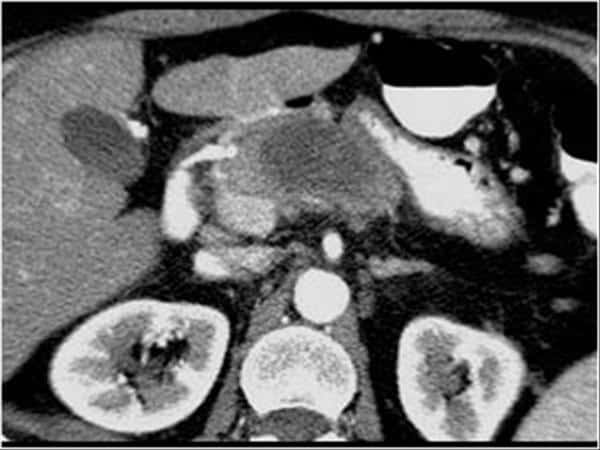

U tụy

» Thông tin: Nữ giới – 57 tuổi.

» Lâm sàng: Sút cân.